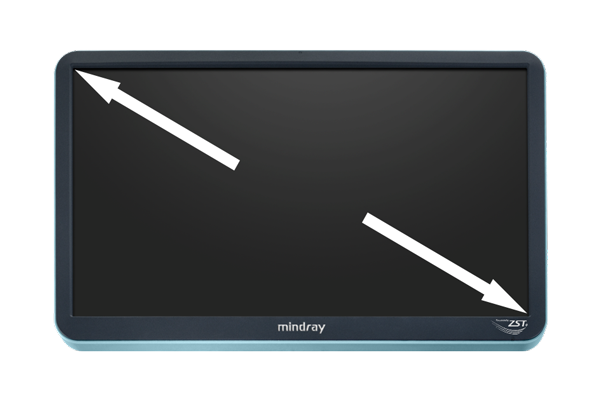

M-Reference E Compare

Strain en shear-wave inspireren samen de toekomst

M-Reference C&E

CEUS en shear-wave ontrafelen samen de multi-parametrische echografiewereld

M-Reference Multi-parametrische analysetools

M-Ref. C&E ondersteunt het weergeven van het contrast en de STE in ├®├®n vlak voor vergelijkende beoordeling van perfusie en elasticiteit.

M-Ref. E Compare

M-Ref. E Compare ondersteunt het weergeven van zowel de realtime strain-elastografie als STE in ├®├®n vlak voor de evaluatie van weefselstijfheid.